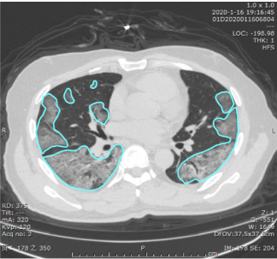

The InferRead CT Pneumonia model traces the outlines of all the lung opacities (more specifically, it identifies all of the pixels that are part of a lung opacity):

Example of lung opacities segmented by the deep learning model in Huang et al.

The percent of lung pixels that are opacified then serves as a quantitative measure of the extent of the lung opacification. A “100% opacified lung” would be all white instead of all black.